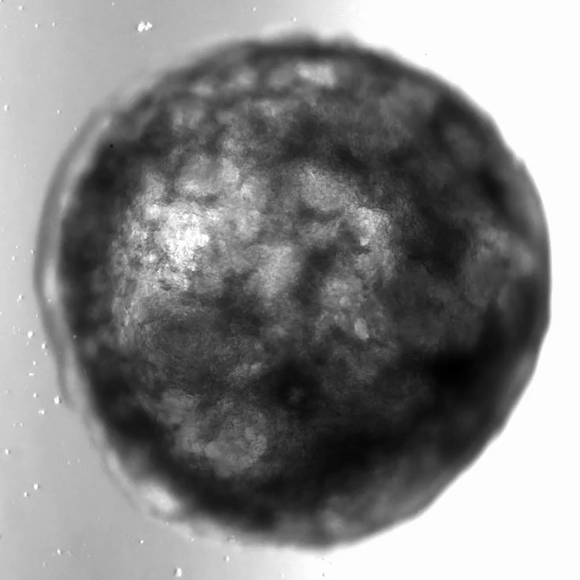

במחקר הנוכחי, שהתפרסם בכתב העת Cell, הצליחו חוקרים בהובלת מדענים מהמכון האוסטרי לביוטכנולוגיה מולקולרית לגרום לתאים להסתדר באופן עצמאי, ללא צורך בתבנית. החוקרים השתמשו בתכונות הטבעיות של התאים וגרמו להם לבנות לב שלם באמצעות חשיפתם לחומרים מסוימים. אומנם מדובר רק במיני-איבר, בגודל של גרגיר סומסום, אך עדיין מדובר באירוע משמעותי. בתוך צבר התאים הזעיר הזה נוצר חלל שהמבנה שלו מזכיר את ארבעת חדרי הלב, והוא אפילו פועם – כלומר מזרים דרכו נוזלים כפי שהלב מזרים את הדם.

מתכווץ, מתרחב ומזרים נוזלים, למרות גודלו הזעיר. אורגנואיד הלב בפעולה | צילום: The Mendjan Lab